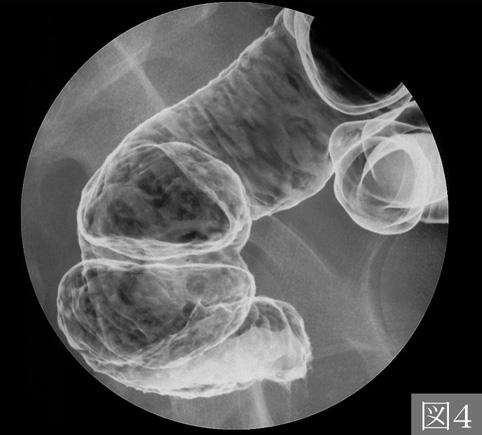

A case of amebiasis which showed the typical morphologic findings corresponding to the amebic colitis.

염증성 및 궤양성질환/아메바성 대장염

대장/2구역 이상의 대장에 걸치는 것

X-P